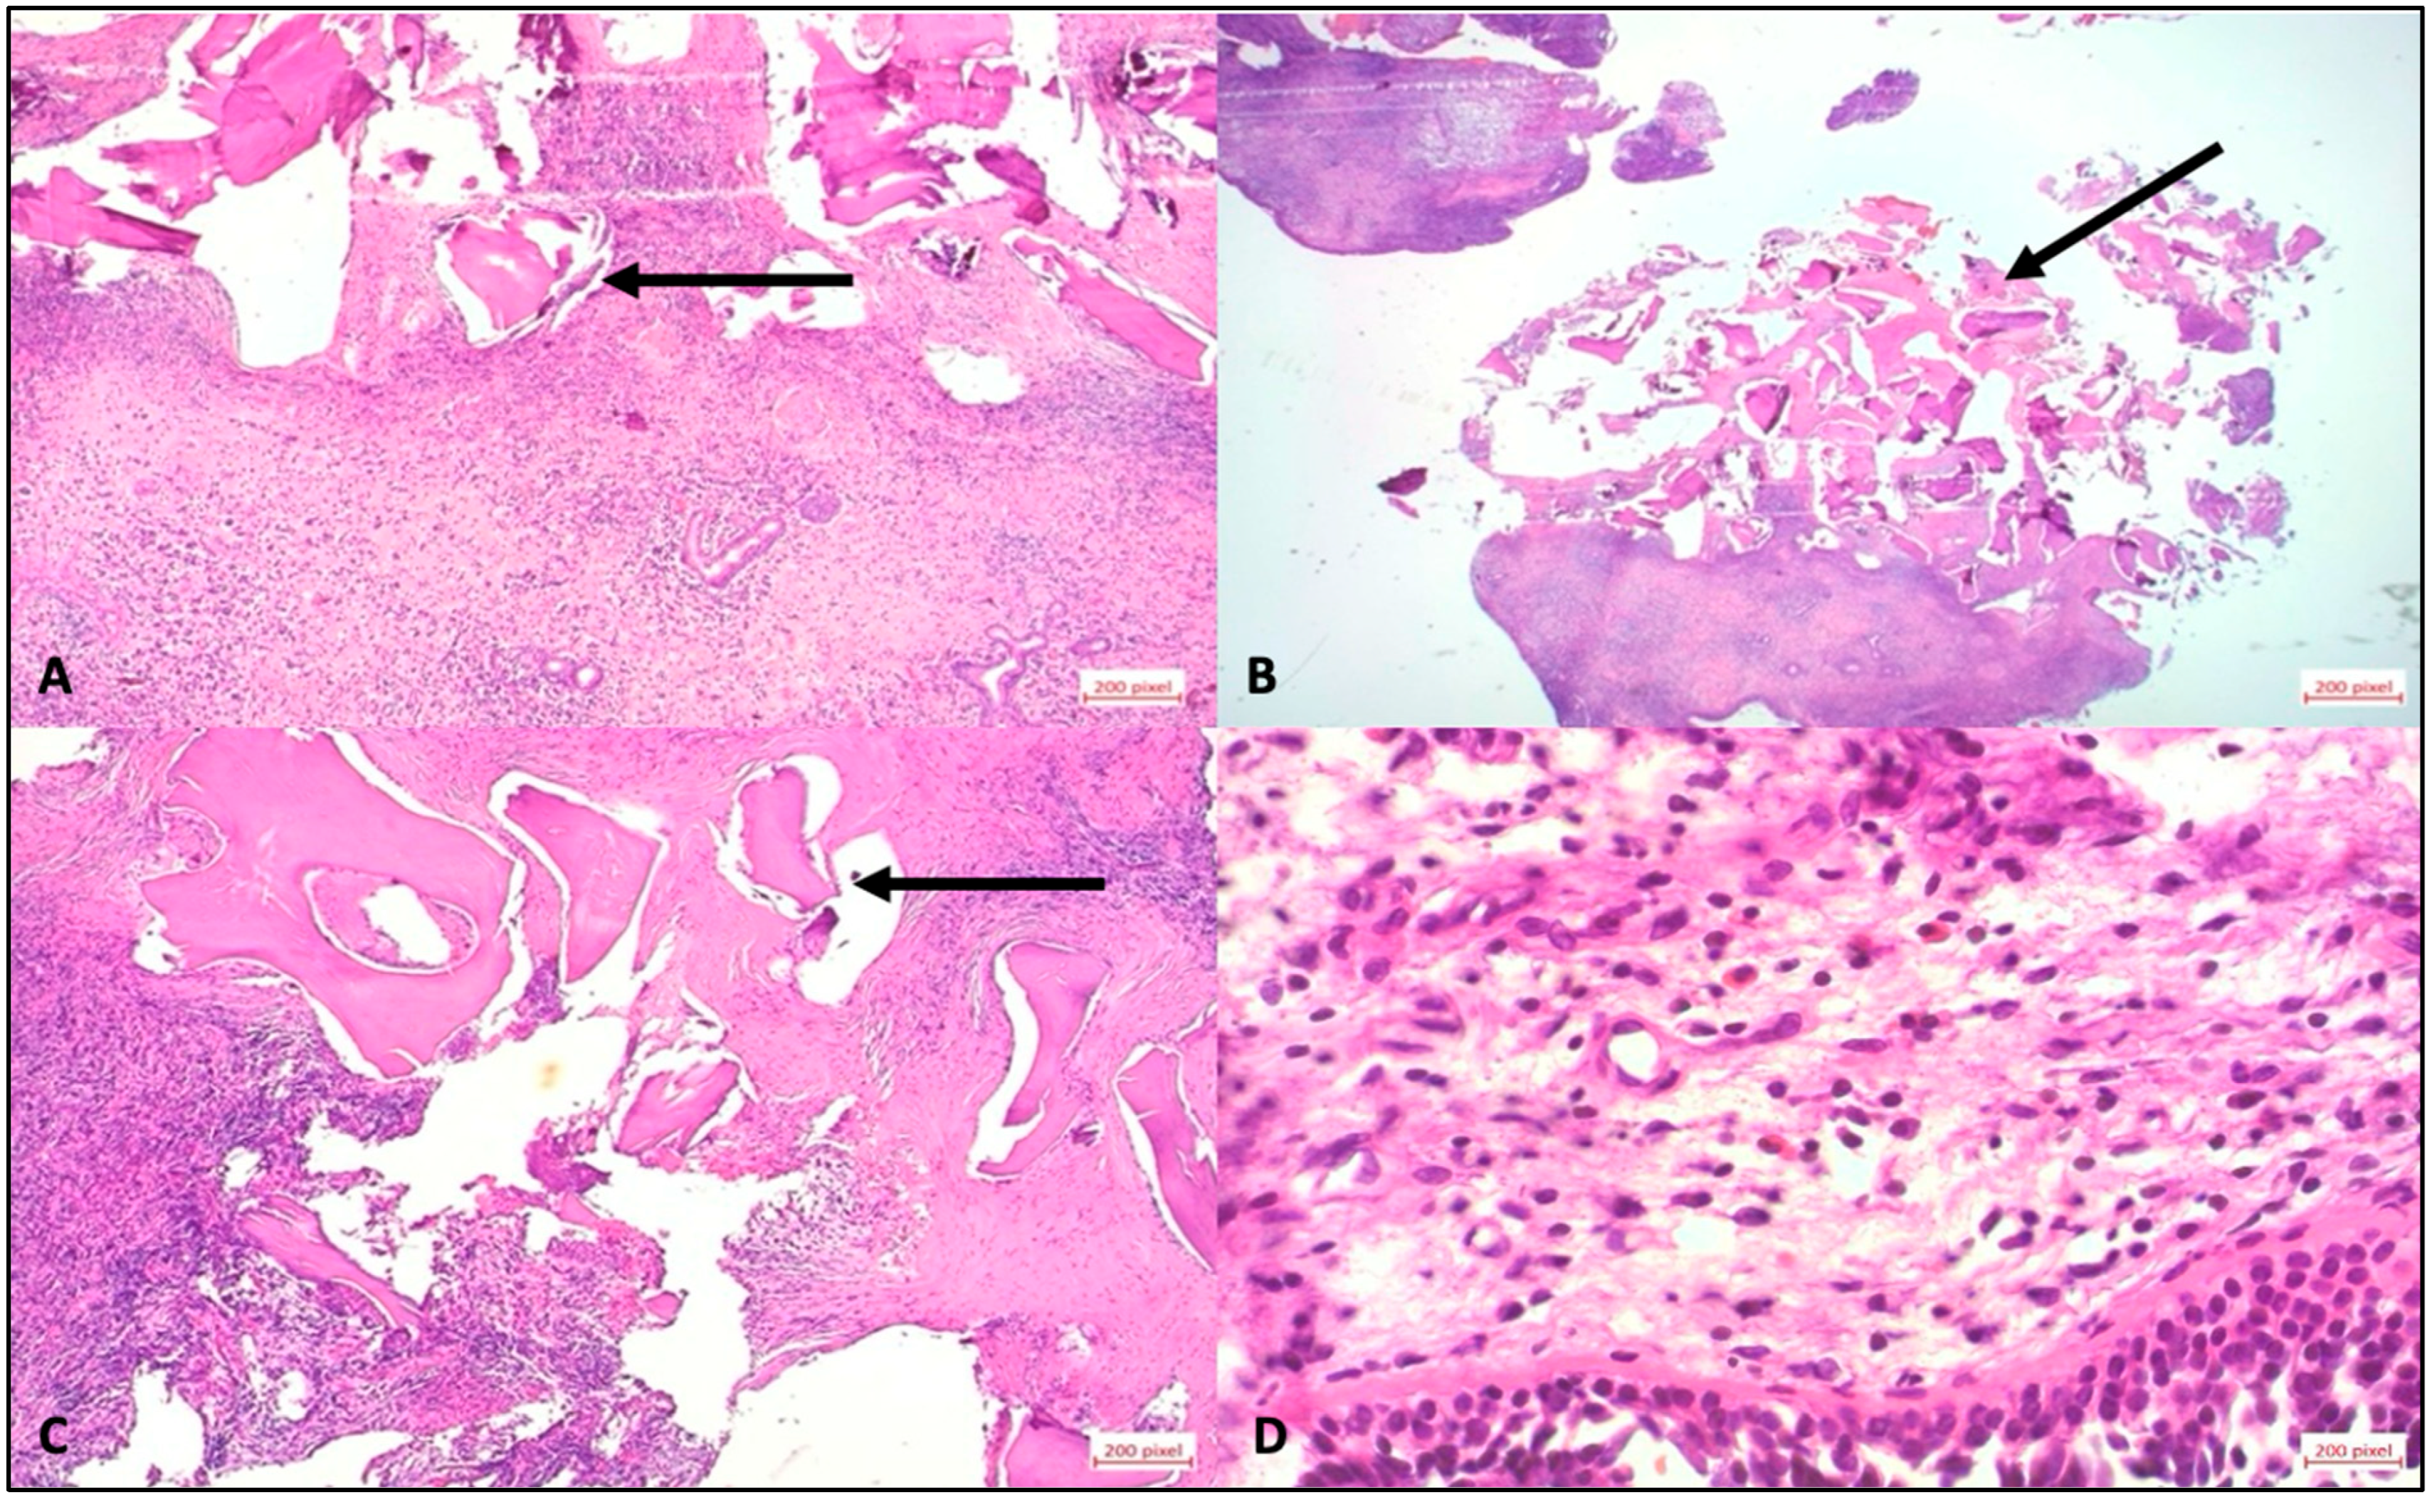

Figure 4. Histological images of a stained with hematoxylin and eosin using a staining device. (A) Bone fragments of different sizes, surrounded by connective tissue. Numerous lymphocytes and plasma cells in the parts of the stroma close to the mucosa; these inflammatory changes extend to the bone fragments close to the surface. (B) Bone fragments of different sizes; highly dense inflammatory stroma and epithelium. (C) Black arrow: Stroma with inflammatory cells, extending to the bone parts close to the mucosa. (D) Mucosal epithelium; minimally edematous stroma with small vessels; and lymphocytes, plasma cells and eosinophilic granulocytes in the stroma.

A total of 9 out of 47 patients (19.1%) developed atypical late complications and radiological evaluation of the ROI was performed to investigate the relationship between bone availability and complication risk. The median time to the first complication was 645 days (IQR 449–686). Atypical complications were distributed as follows in patients with MSFA and simultaneous implantation: two patients experienced pain between 322 (ROI 55.06 mm2) and 636 days (ROI 25.2 mm2) after surgery, thus delaying the prosthetic restoration. One patient suffered a loss of one of the two implants placed during the impression (distal implant with little residual bone (ROI 55.32 mm2 vs. ROI 13.12 mm2) 842 days after surgery (Figure 3B). In patients with MSFA and delayed implantation, one patient lost the implant and bone graft substitute at 752 days (ROI of 8.1 mm2). A second patient showed clinical discomfort at 640 days (ROI of 5.16 mm2). A third patient lost the implant during prosthetic impression at 612 days (ROI 14.07 mm2). A fourth patient exhibited a lack of osseointegration of the implant 938 days after MSFA (ROI 19.55 mm2). A fifth patient lost the implant and bone graft substitute at 781 days (ROI of 9.46 mm2) (Figure 3C). A sixth patient showed a fistula formation 634 days after surgery (Figure 3A) and exhibited a lack of osseointegration of the bone graft substitute; finally, the bone graft substitute was explanted after 940 days of MSFA (ROI of 0, considered non-measurable) (Figure 3D–F). In all the patients described, a decision was made to perform a new operation and remove bone replacement material due to the complications that occurred. Immediately after the surgery, the tissue was placed in sample containers containing 4.5% formaldehyde. Each sample was assigned a unique patient-specific identification number and macroscopically assessed according to size, color, consistency, and recognizable abnormalities. The tissue was then cut according to size and placed in an embedding cassette labeled with the patient number. According to standardized methods of sample preparation, the pathologist provided a diagnosis after examining the tissue using light microscopy and the polarization technique, which is used to detect foreign material with double refraction (Figure 4).